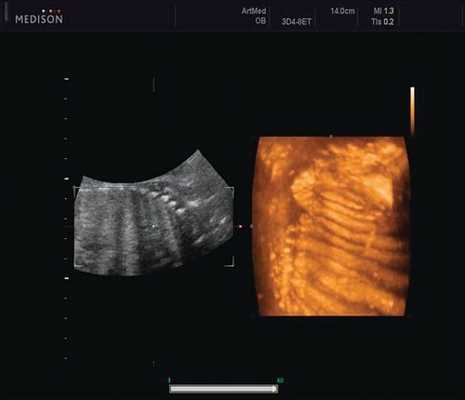

Революцией в пренатальной ультразвуковой диагностике явилось появление объемной эхографии, которая, обладая такими качествами, как неинвазивность, безопасность и возможность многократного применения у одной пациентки, имеет высокую информативность в исследовании анатомии плода и изучении его фенотипа. При применении различных режимов объемной эхографии абсолютно очевидно их преимущество по сравнению с обычным сканированием. Детально можно изучить лицо плода (рис. 1-4) в различные сроки беременности, начиная со сроков первого пренатального скрининга в 11-14 нед, конечности плода, причем не только их наличие и положение (рис. 5, 6), но и состояние и количество пальцев (рис. 7-9) как на руках, так и на ногах. Также можно изучить позвонки плода (рис. 10), состояние твердого нёба (рис. 11, 12), строение наружного уха (ушной раковины) (рис. 13), состояние основных швов черепа и родничков, исключая их преждевременное закрытие при кранисиностозах (рис. 14, 15).

Пациентка К., 26 лет, обратилась в клинику в 23 нед беременности. Беременность первая. Исследование проводилось на аппарате Accuvix-XQ (Samsung Medison) с использованием режима поверхностной объемной реконструкции 3D/4D. Показатели фетометрии полностью соответствовали сроку беременности. В процессе сканирования позвоночника во фронтальной и сагиттальной плоскостях выявлена угловая деформация позвоночника в грудном отделе, протяженностью около трех позвонков. В поперечной плоскости сканирования нарушения структур и целостности тканей не было обнаружено. В режиме 3D/4D реконструкции было выявлено асимметричное расхождение ребер правой и левой стороны грудной клетки (рис. 4).

Ребра левой стороны были сближены, межреберные промежутки уменьшены по сравнению с противоположной стороной (рис. 5, 6). Другой патологии у плода не было выявлено. Заподозрен врожденный сколиоз, основой которого является наличие боковых полупозвонков (hemivertebrae) или боковых клиновидных позвонков. В 26 нед ультразвуковая картина сохранялась. При проведении трехмерной эхографии получено отчетливое изображение асимметрии реберных дуг и сколиотическая деформация позвоночника.